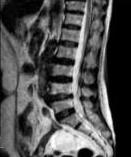

• 单侧双通道内镜与经皮椎间孔镜技术治疗极外侧型腰椎间盘突出症的临床疗效对比

摘要:目的 比较单侧双通道内镜(UBE)与经皮椎间孔镜下髓核摘除术(PTED)治疗极外侧型腰椎间盘突出症(FLLDH)的临床疗效。方法 回顾性分析2021年3月-2023年3月于该院进行治疗的FLLDH患者42例,根据手术方法不同,将患者分为UBE组(18例)和PTED组(24例)。记录并比较两组患者手术时间、术中透视次数、住院时间和围手术期并发症等指标。采用疼痛视觉模拟法(VAS)评估疼痛程度,Oswestry功能障碍指数(ODI)评估功能障碍情况,Macnab评分标准评估临床疗效。结果 UBE组手术时间为(95.56±20.94)min,较PTED组的(78.25±17.23)min长,术中出血量为(69.17±8.95)mL,较PTED组的(23.96±5.89)mL多,差异均有统计学意义(P < 0.05)。UBE组住院时间为(5.67±1.28)d,与PTED组的(5.33±1.05)d比较,差异无统计学意义(P > 0.05)。UBE组术中透视次数为(3.00±0.77)次,明显少于PTED组的(7.42±0.93)次,差异有统计学意义(P < 0.05)。两组患者术后VAS评分和ODI较术前明显降低,差异均有统计学意义(P < 0.05)。术后3 d,UBE组腿痛VAS评分为(3.28±0.58)分及ODI为(41.17±4.30)%,明显低于PTED组的(4.13±0.74)分及(45.50±3.91)%,差异均有统计学意义(P < 0.05),但两组患者术后3个月和1年的VAS评分及ODI比较,差异均无统计学意义(P > 0.05)。两组患者优良率比较,差异无统计学意义(88.9%和87.5%,P = 0.563)。PTED组围手术期出现神经损伤2例,UBE组无神经损伤出现,两组均无感染、复发和大出血等严重并发症发生。结论 PTED与UBE两种手术方式治疗FLLDH均安全和有效。但UBE术中透视次数少,镜下视野更加清晰,神经损伤风险更小。